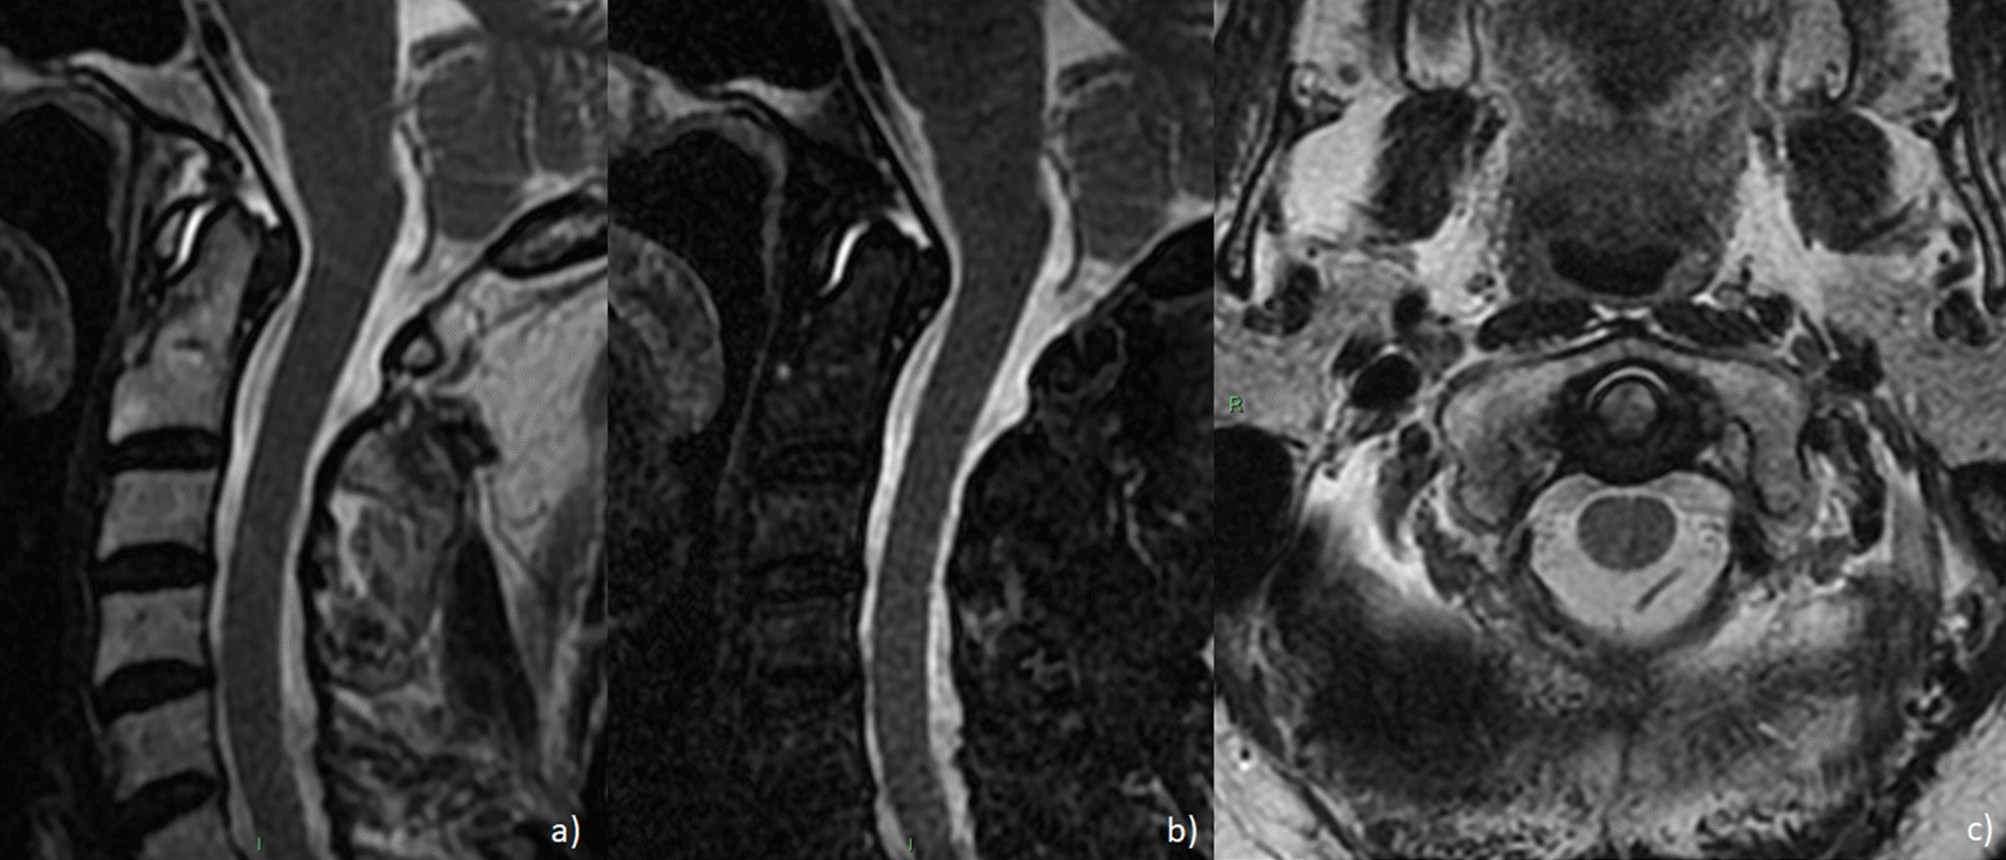

Figure 5

Sagittal T2 (a), sagittal fat-saturated T2 (b) and axial T2 (c) depicting periodontoid joint fluid with posterior thickening of the transverse ligament.